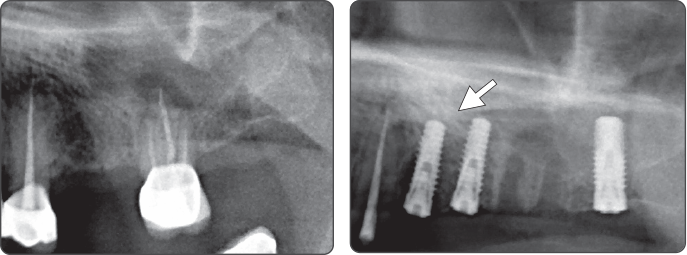

Рекомендуется использовать сверло для синус-лифтинга и уплотнительную фрезу вместе

2. Синус-лифтинг (имплантат Ø5.0)